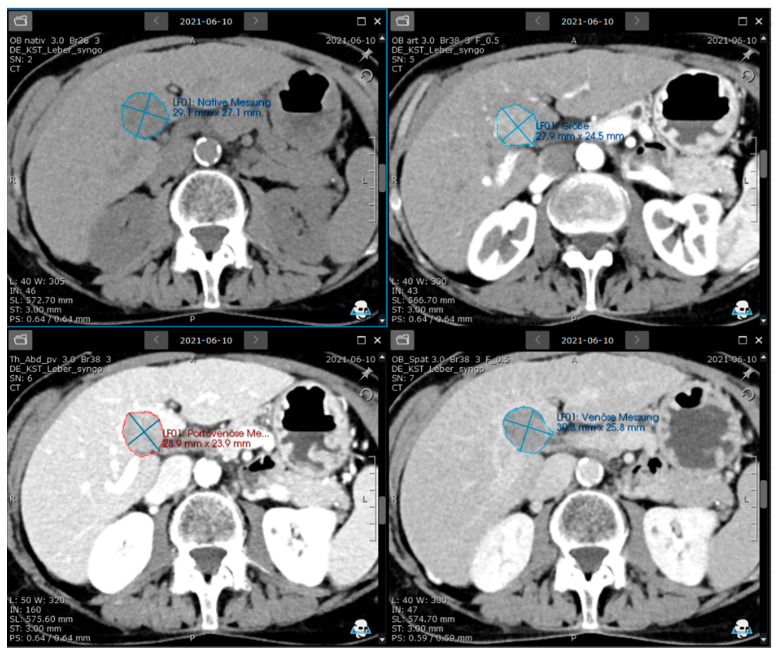

背景/目的:肝细胞癌(HCC)是肝脏最常见的原发性恶性肿瘤。对于肝硬化,每个大于10mm的结节都需要进一步的CT或MRI检查。肝脏成像报告和数据系统(LI-RADS)仍然是基于视觉评估和测量。本研究的目的是评估视觉LR-5病变的半自动化量化是否合适,是否可以客观地进行HCC分类,以进行个性化放射学研究。方法:回顾性数据收集的52例HCC患者(中位年龄67岁,女性17%,男性83%)使用具有基于li - rad的结构化肿瘤评估和记录、半自动肿瘤分割和纹理分析功能的肿瘤软件进行视觉评估和结果比较。结果:基于软件的非边缘动脉期高增强(APHE)和非外周洗脱以及li - rad评分与视觉评估相比无统计学差异(p = 0.2, 0.7, 0.17),人类读者与软件方法的一致性分别为98% (APHE), 89%(洗脱)和93%(阈值增长)。该软件为HCC登记和放射学研究提供了自动LI-RADS分类、结构化报告和定量特征。结论:本研究为基于li - rad的自动定性和定量评价提供了前景。未来的研究可能会显示纹理分析是否可以用于肝癌的个性化医疗方法。

Methods: A total of 52 HCC patients (median age 67 years, 17% females, 83% males) from a retrospective data collection were evaluated visually and compared by the results using an oncology software with features of LI-RADS-based structured tumour evaluation and documentation, semi-automated tumour segmentation, and texture analysis.